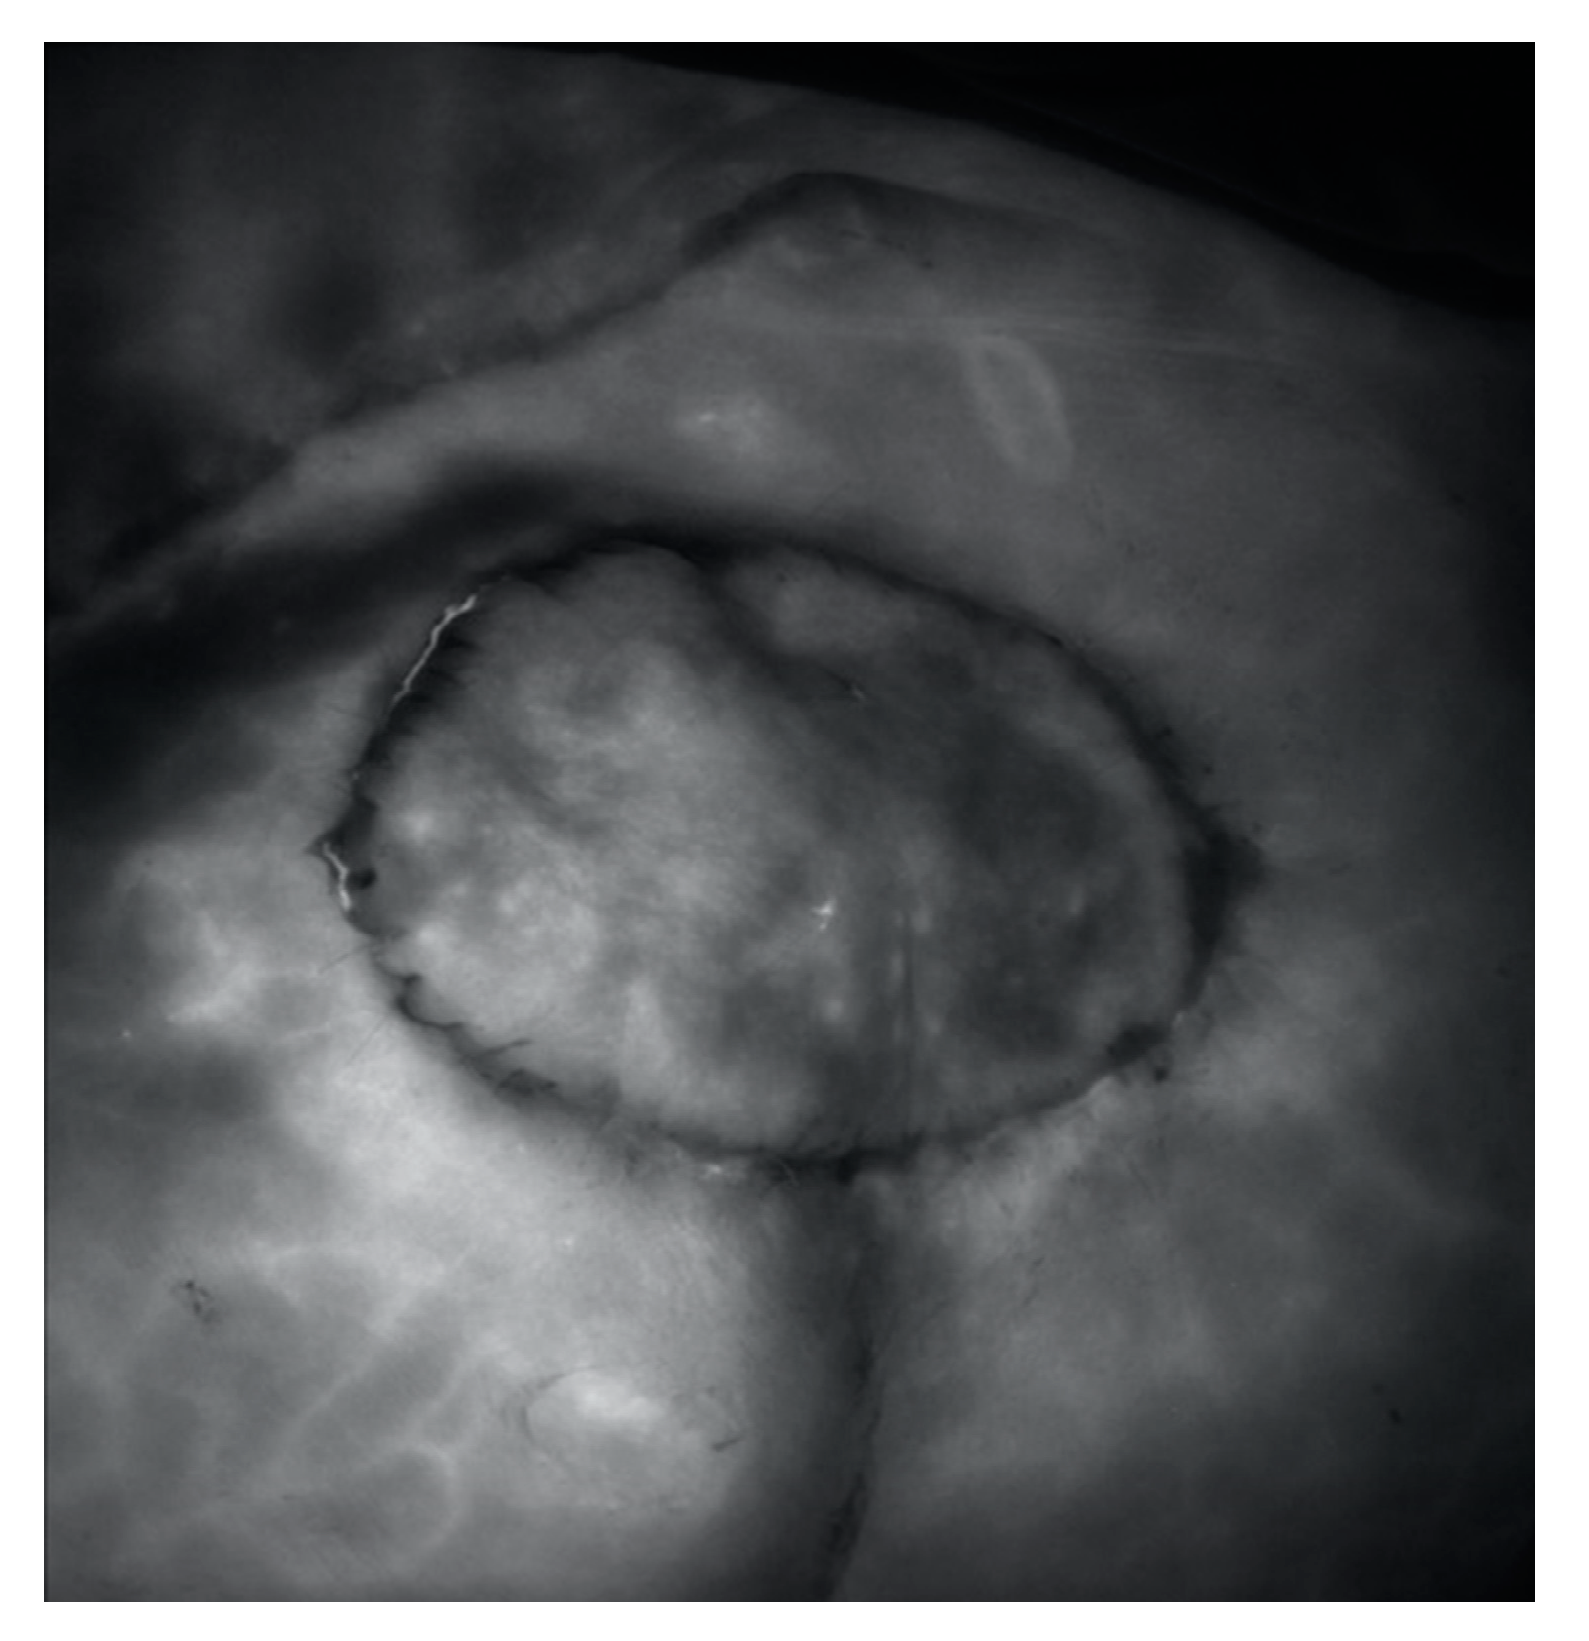

Traditionally, handheld ADS is an effective way of detecting the perforators of the SGAP flap (Figure 5). Plastic and reconstructive surgery has always been on the frontier of utilizing novel and innovative technologies to improve patient safety during operative procedures. ICG is a water-soluble tricarbocyanine dye that fluoresces upon exposure to near-infrared light. This fluorescence can be detected using a stereoscopic camera [6]. ICG fluorescent angiography is generally performed intraoperatively before or after harvesting the flap to mark the area of likely flap survival. ICG fluorescent angiography was used to confirm a dynamic blood flow and provide a final confirmation of the perioperative posture of the perforators. This technique is also useful for determining which perforating branch is dominant [3].

Figure 5. ICG fluorescent angiography was used to confirm a dynamic blood flow and provide a final confirmation of the perioperative posture of the perforators.